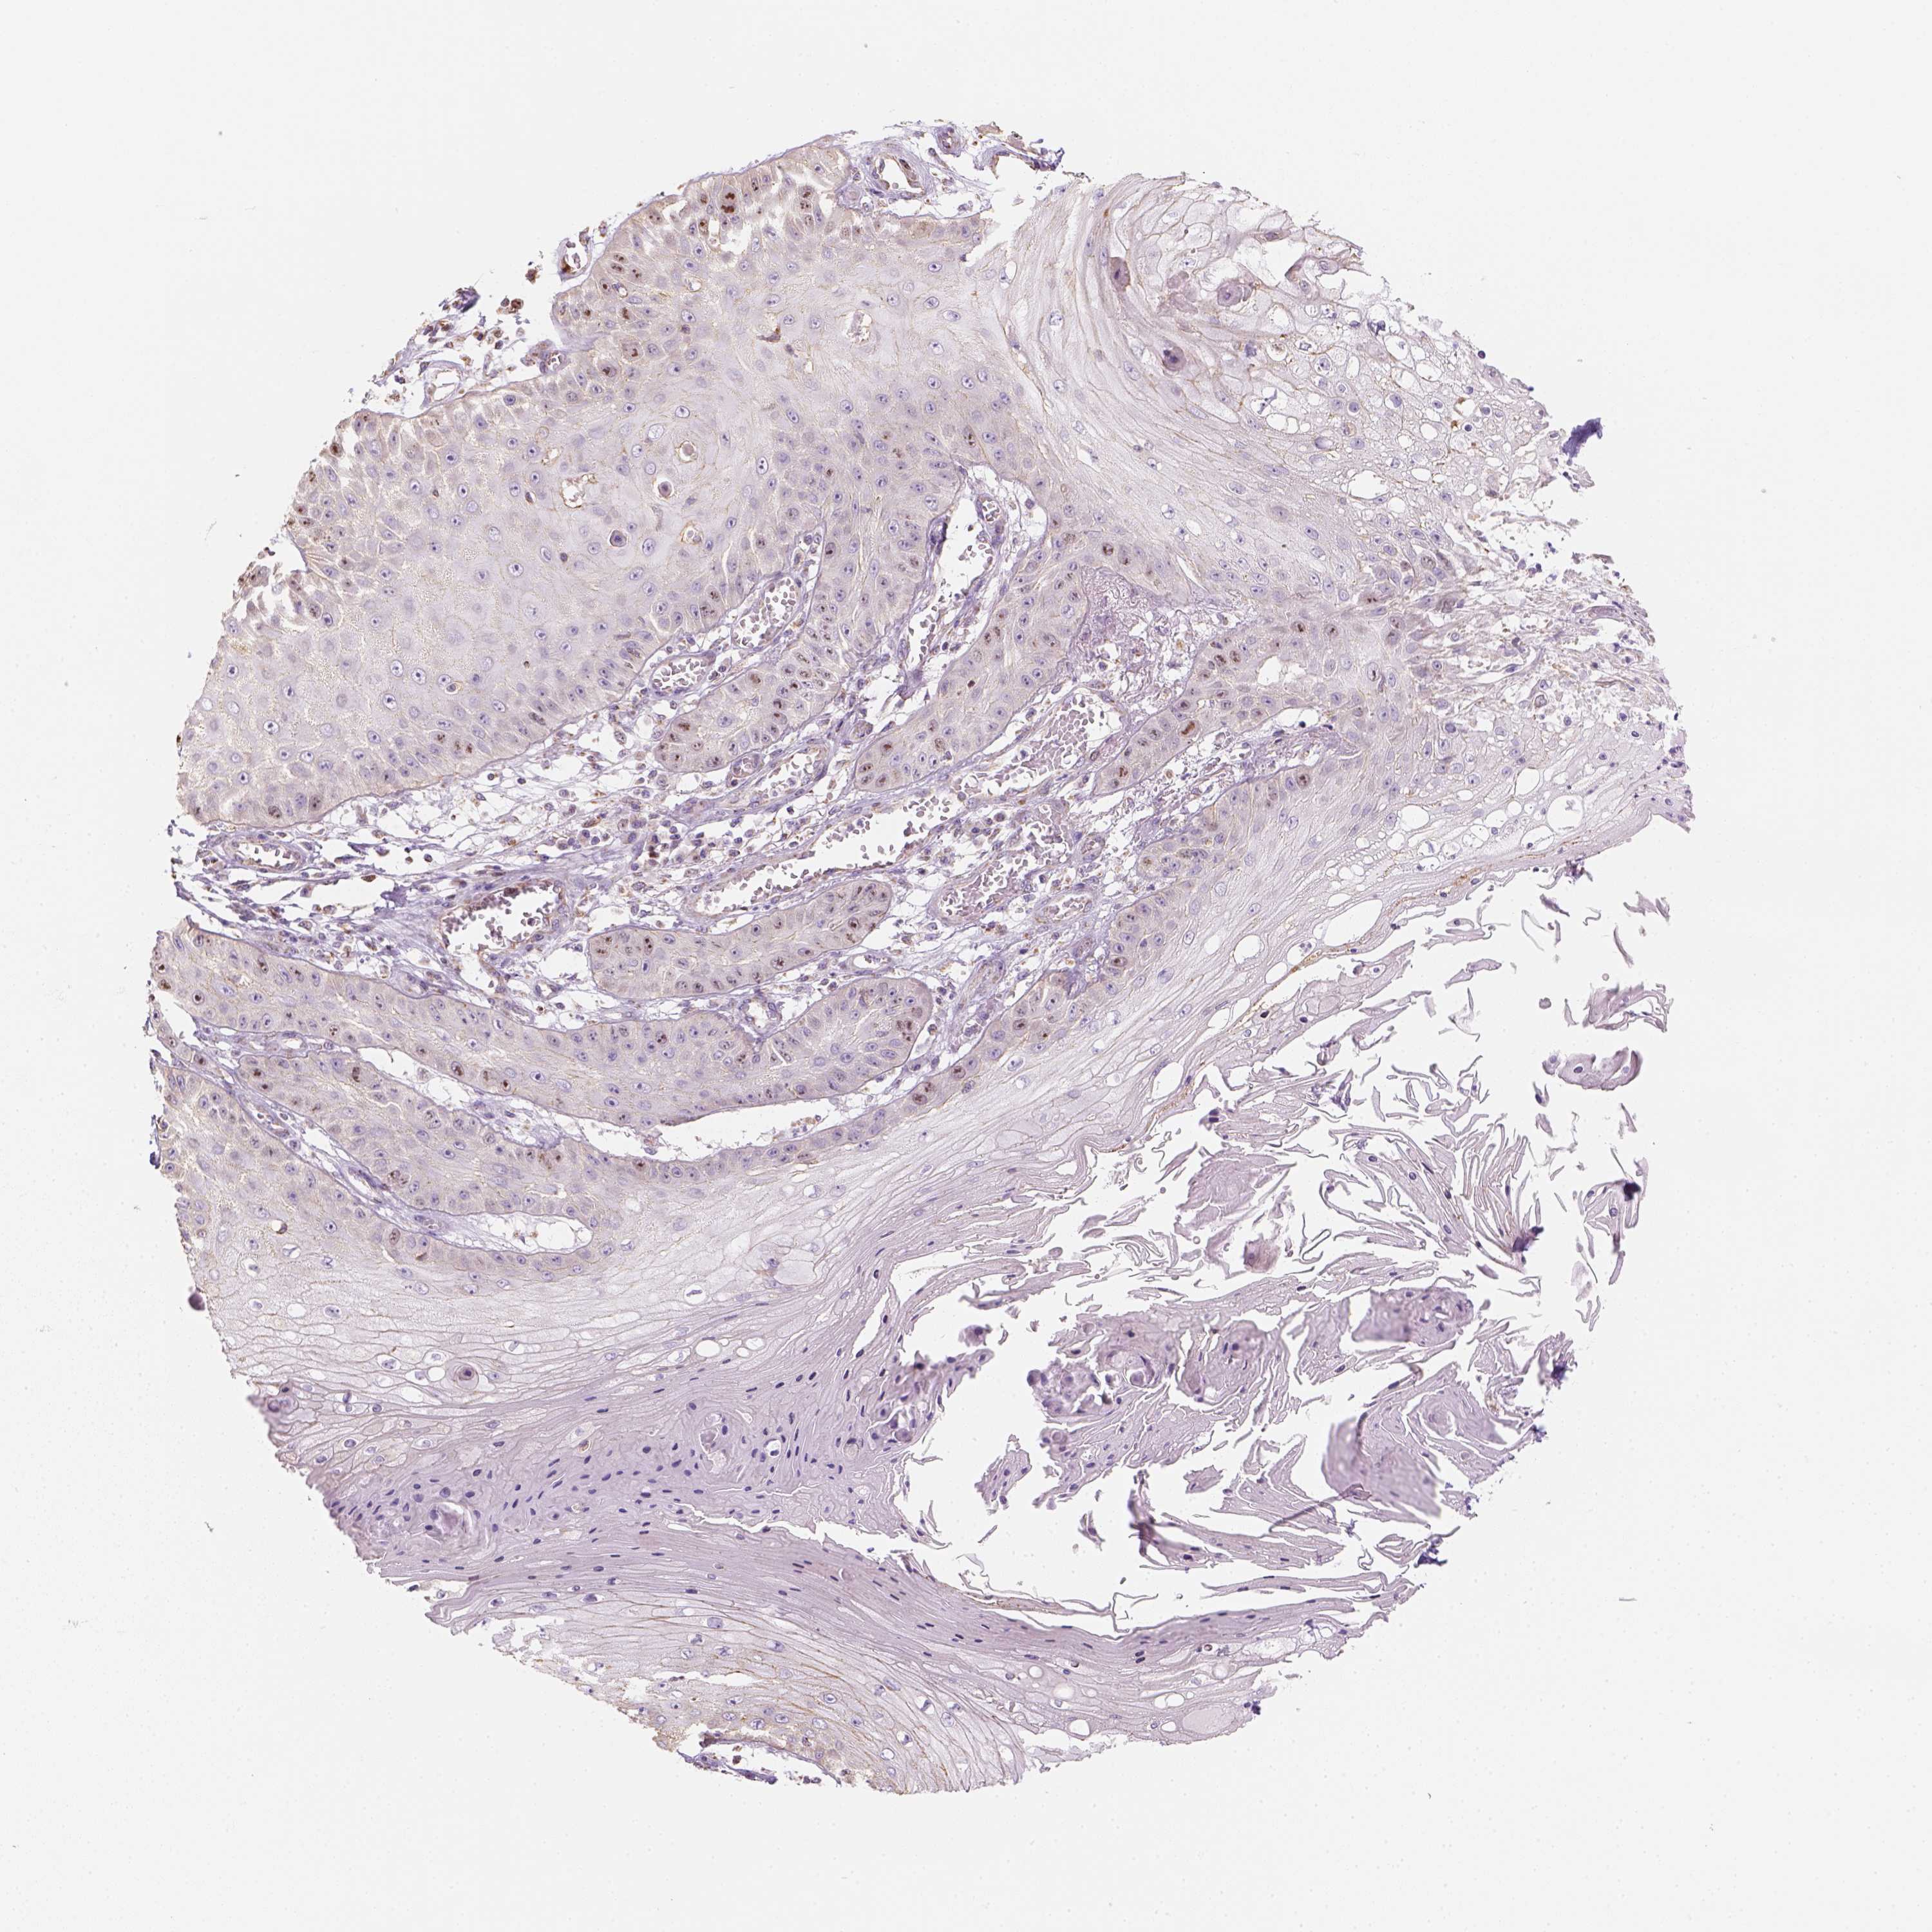

Basal cell and squamous cell cancer

SKIN CANCER - Protein expressioni

A mouse-over function shows sample information and annotation data. Click on an image to view it in a full screen mode. Samples can be filtered based on level of antibody staining by selecting one or several of the following categories: high, medium, low and not detected. The assay and annotation is described here.

Antibody stainingi

Antibody staining in the annotated cell types in the current human tissue is reported as not detected, low, medium, or high, based on conventional immunohistochemistry profiling in selected tissues. This score is based on the combination of the staining intensity and fraction of stained cells.

Each image is clickable and will lead to virtual microscopy that enables deeper exploration of all samples and also displays staining intensity scores, fraction scores and subcellular localization as well as patient and tissue information for each sample.

Antibody HPA029053

Antibody HPA029055

Staining

High

Medium

Low

Not detected

Intensity

Strong

Moderate

Weak

Negative

Quantity

>75%

75%-25%

<25%

None

Location

Nuclear

Cytoplasmic/membranous

Cytoplasmic/membranous,nuclear

Basal cell carcinoma